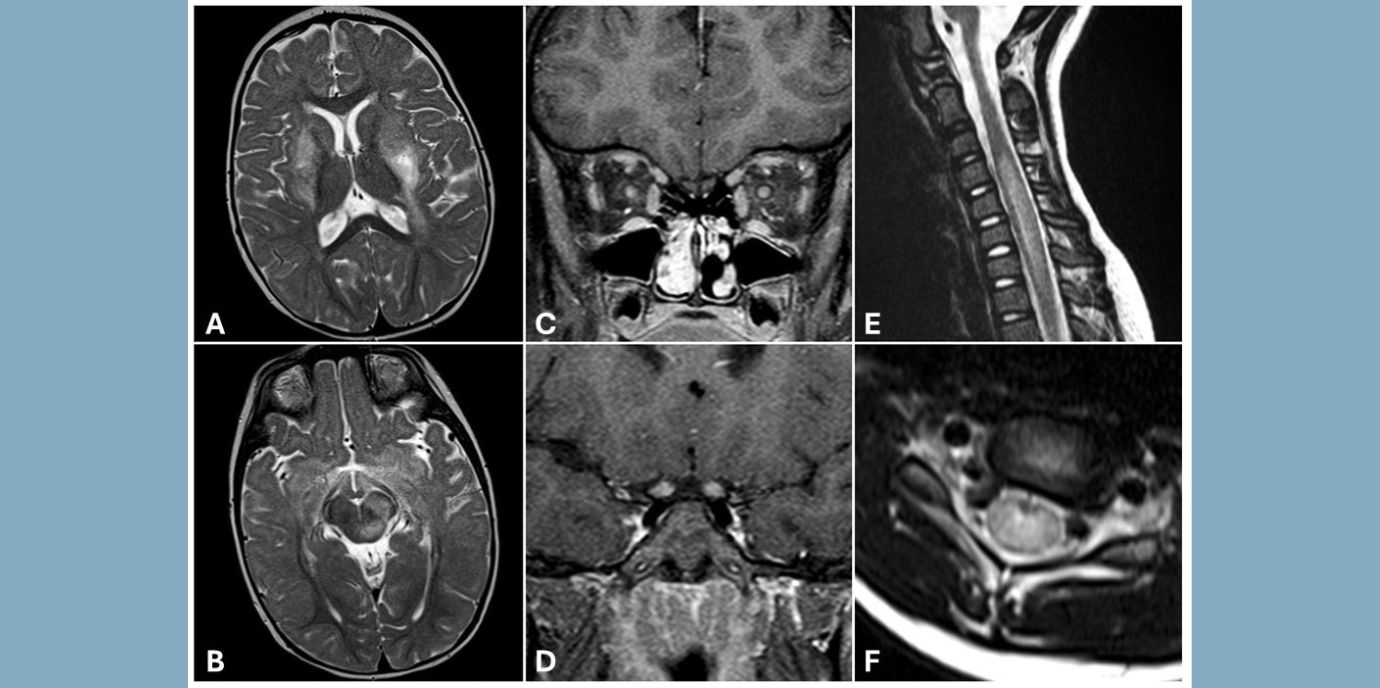

Auf den ersten Blick ist MOGAD schwer von ähnlichen Krankheiten, wie z.B. Multiple Sklerose oder NMOSD (Neuromyelitis Optica Spektrum-Erkrankungen) zu unterscheiden. Allerdings wurden 2004 krankheitsspezifische Antikörper gegen Aquaporin-4 bei NMOSD-Patient:innen entdeckt, wie Christian Lechner schildert.

*MOGAD (Myelin Oligodendrocyte Glycoprotein Antibody-associated Disorders) sind entzündliche Erkrankungen des Zentralnervensystems mit unterschiedlichen Ausprägungen bzw. Subtypen. Bei Kindern dominiert meist ADEM (Acute Disseminated Encephalomyelitis), das von einer Enzephalopathie (Bewusstseinsstörung), häufig gepaart mit Koordinations- und motorischen Schwierigkeiten, Übelkeit und Kopfschmerzen charakterisiert ist, während Jugendliche und Erwachsene mehr von Optikusneuritis, einer Sehnerventzündung, betroffen sind. LETM (Transverse Myelitis bzw. Longitudinal Extensive Transverse Myelitis) trifft ebenso eher Jugendliche und Erwachsene und ist hauptsächlich durch Lähmungserscheinungen gekennzeichnet. Bis zur Hälfte aller MOGAD-Patient:innen sind von einem schubhaften Verlauf (multiphasisch) betroffen, während die übrigen an MOGAD Erkrankten eine einmalige, akute Krankheitsphase erleben.